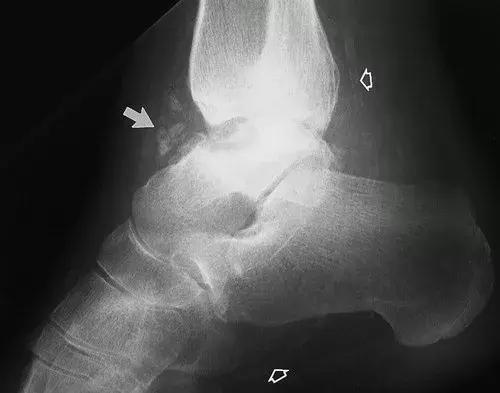

图15:27岁女性糖尿病人,踝关节的神经性骨关节病。侧位X线片显示了大的踝关节积液,其具有碎裂和胫骨关节塌陷(实线箭头)。 存在微血管钙化(空心箭头),表明糖尿病是神经性骨关节病的原因。 虽然不如脚的神经性畸形常见,但糖尿病神经病变患者也会发生神经性踝关节改变。